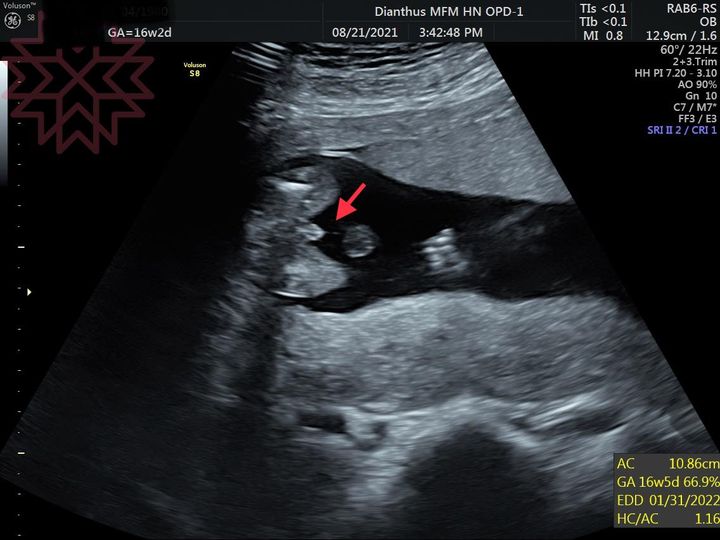

用超音波看男寶寶還是女寶寶

https://drsu.blog/2021/04/14/super210414/